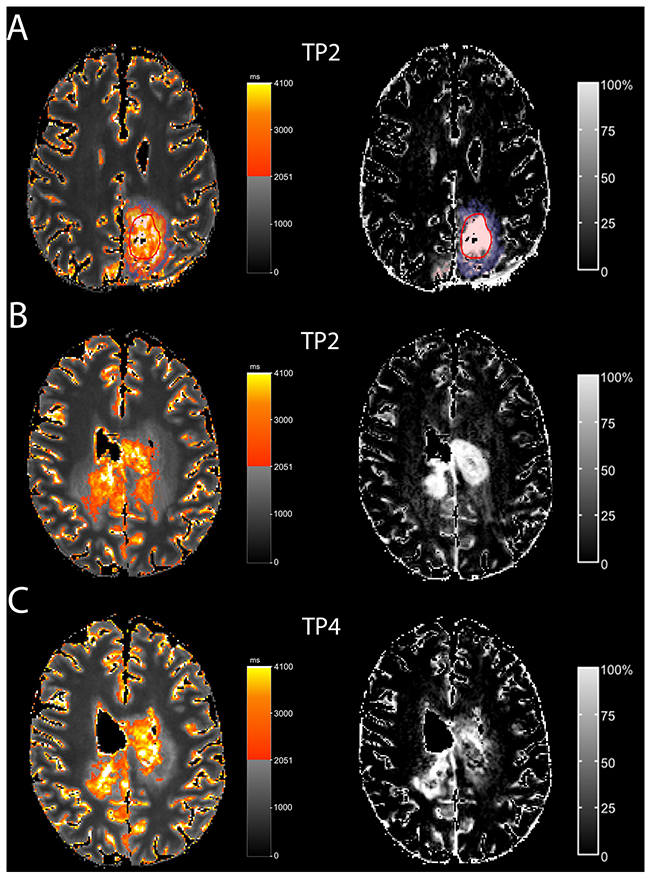

In five patients (Table 1, patients 2,3,7,8,9), the qT1-prolonged area was restricted to the contrast-enhancing tumor. In the remaining five patients, the qT1-prolonged area extended beyond the contrast-enhancing tumor (Figure 3 and 4 show this in exemplary fashion for patients 5 and 6). The qT1-prolonged area outside the contrast-enhancing tumor partially matched the subtle contrast-enhancement surrounding the solid contrast-enhancement (Figure 4A shows this in exemplary fashion for patient 5). Small parts of these areas transformed to contrast-enhancing tumor at the time of progression in four patients (Patients 1,4,5,6) (Figure 4B and 4C show this in exemplary fashion for patient 6), or at a later timepoint (n=1, patient 4). Interestingly, three of the five patients (Patients 1,4,5) with the qT1-prolonged area outside the contrast-enhancing tumor had prior partial resection or biopsy with substantial remaining tumor burden.

Figure 4: T1-prolongation > 2051 ms outside the solid contrast-enhancing tumor In one patient (A; patient 5), T1-prolongation >2051 ms outside the solid contrast-enhancing tumor (red circle) partially fitted with the subtle enhancement (ΔqT1, blue). In another patient (B, C; pat 6), T1-prolongation >2051 ms outside the solid contrast-enhancing tumor at TP 2 (B) partially matched subtle enhancement (ΔqT1). At TP4 (C), this area transformed to contrast-enhancing tumor.